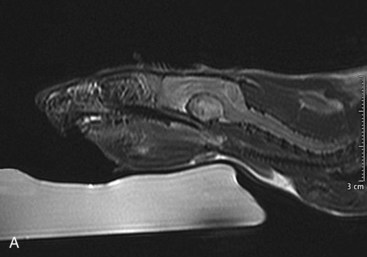

Mammary and Pituitary Tumors A, A pituitary tumor of a rat imaged with an MRI scan. B, The same tumor as in the previous image a few weeks after treatment with cabergoline. Note the significant shrinking of the tumor. (Photo courtesy Jörg Mayer, The University of Georgia, Athens.)